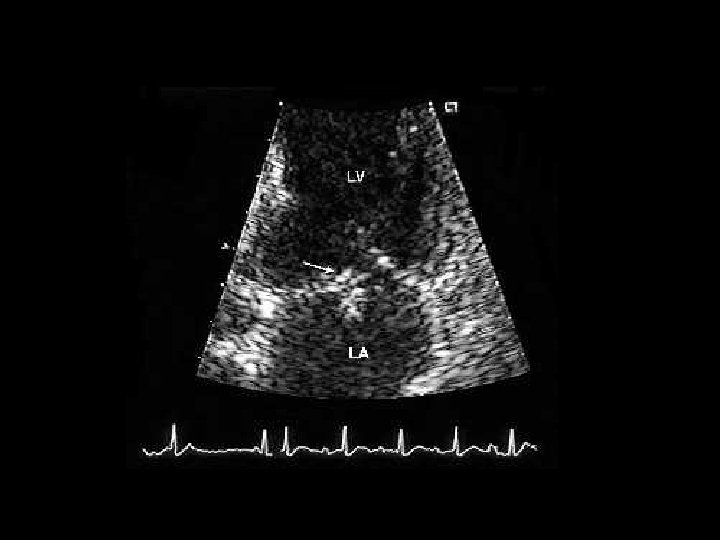

Clínica y diagnóstico o Métodos de diagnóstico por imágenes n Ventriculografía izquierda n Ecocardiografía n TAC n Resonancia magnética

Clínica y diagnóstico o o El soplo puede ser resultado de una CIV o de insuficiencia mitral, ambas condiciones pueden coexistir. Ecocardiograma (TT o TE): Alta sensibilidad y especificidad, seguro, y rápido.